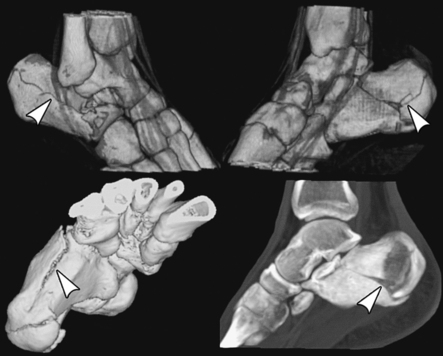

Structures shown: The resulting image shows an axial projection of the calcaneus and the subtalar joint (Fig. 6-78). CT is often used to show this bone (Fig. 6-79).

Fig. 6-79 CT images of calcaneal fracture with three-dimensional reconstruction. Conventional x-ray shows most fractures; however, complex regions, such as calcaneal-talar area, are best shown on CT. Note how bone (arrows) shows extent of fracture. (From Jackson SA, Thomas RM: Cross-sectional imaging made easy, New York, 2004, Churchill Livingstone.) Churchill Livingstone